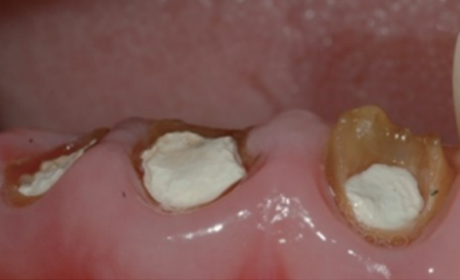

크라운을 씌우기 전 치아안쪽에 기둥을 세우고 보강해주는 과정이 필요합니다.

치아의 길이가 너무 짧은 경우는 치아의 길이를 늘리는 수술이 필요하기도 합니다.